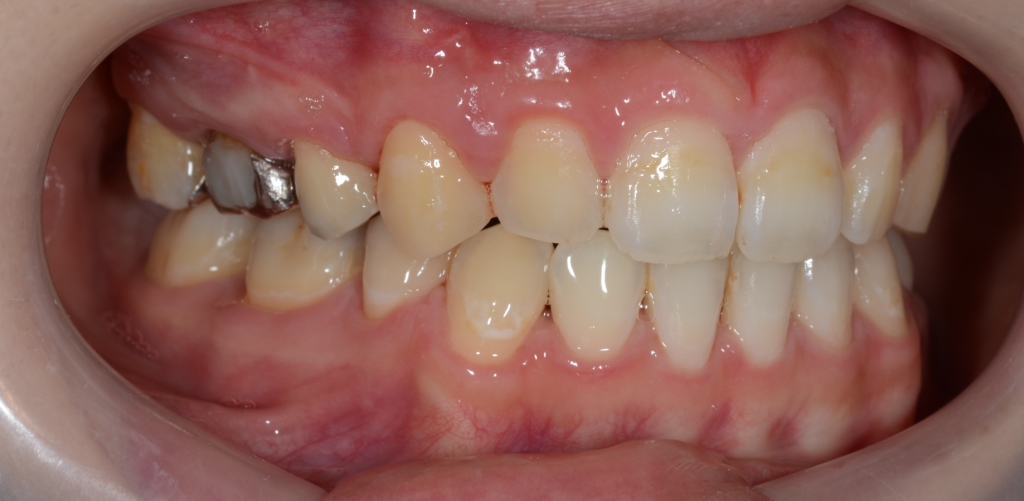

【Before】

レントゲン写真で確認すると、

この患者さんの場合、

【診断】

#1.上顎前歯部が下方へ位置していることによるガミースマイル

#2.上下顎前突(歯槽性)

噛み合わせの関係はノーマル。

と診断しました。